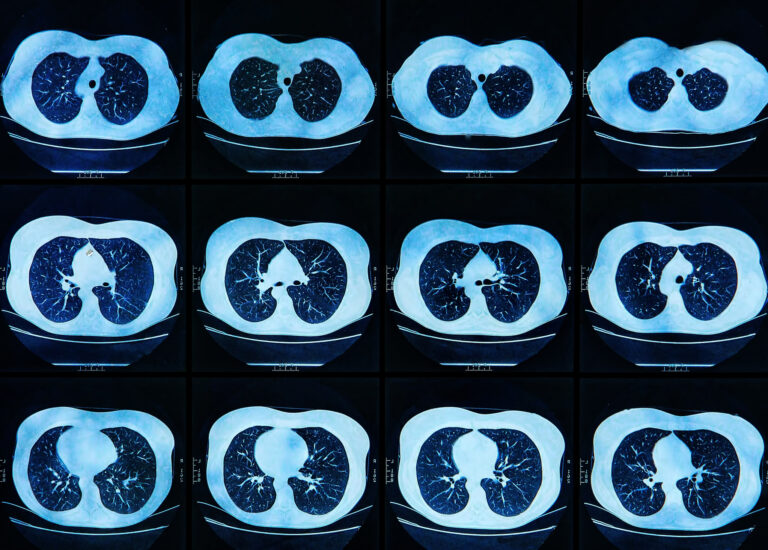

Traditional radiotherapy relies heavily on computed tomography (CT) for treatment planning and delivery. While effective, CT scans often lack the soft tissue contrast necessary to distinguish tumours from surrounding healthy structures, particularly in anatomically complex areas. MRI, with its exceptional soft tissue imaging, overcomes this limitation, enabling clinicians to more accurately define tumour boundaries and adapt treatment plans in real time.

The integration of MRI with linear accelerators (LINACs) has given rise to MRI-guided radiotherapy systems, such as the MR-Linac. These systems allow simultaneous imaging and treatment, enabling real-time monitoring of tumour and organ motion during radiation delivery. This capability is especially beneficial for tumours located in areas subject to significant physiological movement, such as the lungs, abdomen, and pelvis. By continuously visualising the treatment area, clinicians can adjust radiation beams dynamically, ensuring precise targeting even in response to patient breathing or other involuntary movements.